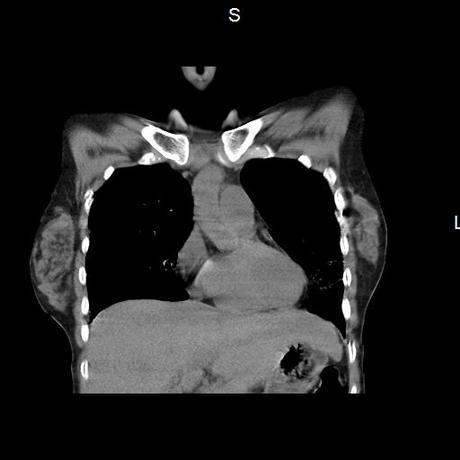

Se realiza volumen de tórax en fase simple, desde los opérculos torácicos hasta los hemidiafragmas, observándose:

El parénquima pulmonar con areas parcheadas difusas en vidrio despulido combinadas con otras areas hipodensas de baja atenuación debidas a atrapamiento aéreo y engrosamiento intersticial y zonas de fibrosis de predominio en lóbulos medios e inferiores de ambos pulmones.

- LOS HALLAZGOS PUEDEN ESTAR EN RELACIÓN A NEUMOPATIA INTERSTICIAL PROBABLE ETIOLOGIA HIPERSENSITIVA VS AUTOINMUNE/BACTERIANA/FUNGICA.